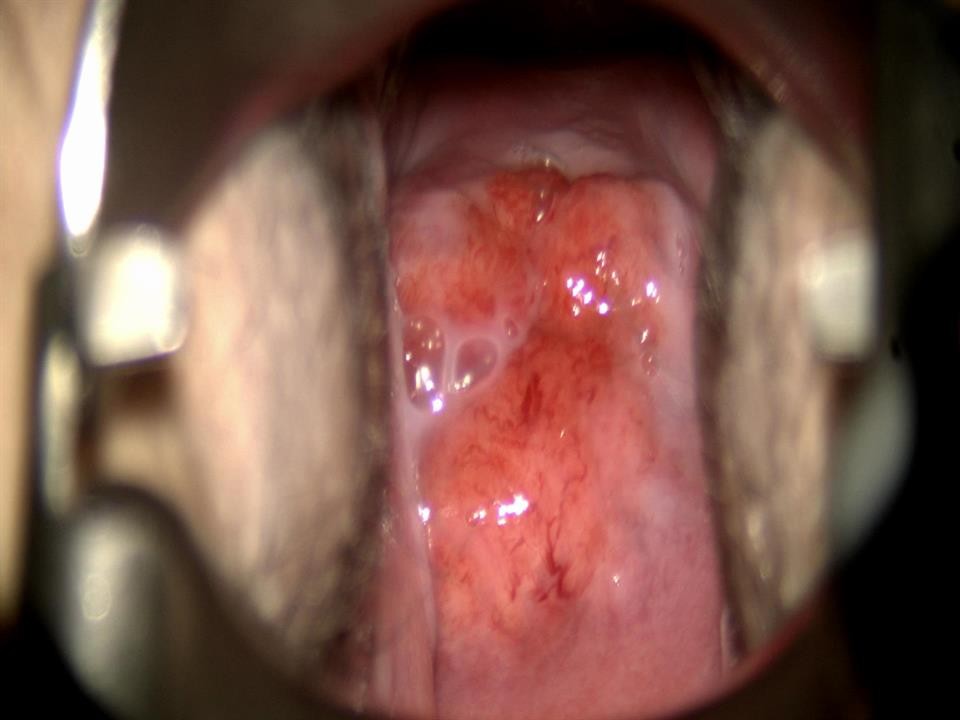

Hình ảnh tổn thương cổ tử cung trước điều trị